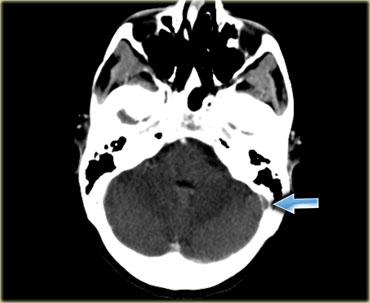

Khối máu tụ giả dấu hiệu mạch máu tăng tỷ trọng.

Thông thường, việc phân biệt khối máu tụ với xoang tĩnh mạch có huyết khối không gặp khó khăn.

Đây là hình ảnh một bệnh nhân có khối máu tụ trong não ở vị trí ngoại vi.

Do vị trí của khối máu tụ nằm trong vùng xoang ngang, nó tạo ra hình ảnh giả xoang ngang có huyết khối.